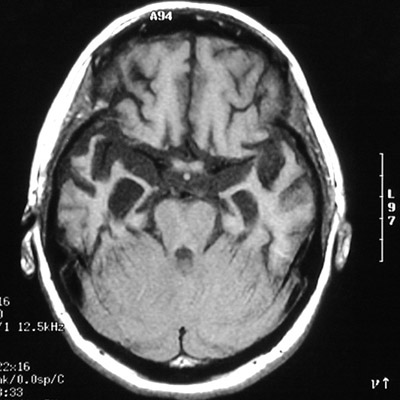

Here is an axial MRI scan demonstrating

marked cerebral atrophy

, mainly involving the temporal lobes in a case of Pick's disease. Note that the gyri are so thin that they have a "knife-like" quality.